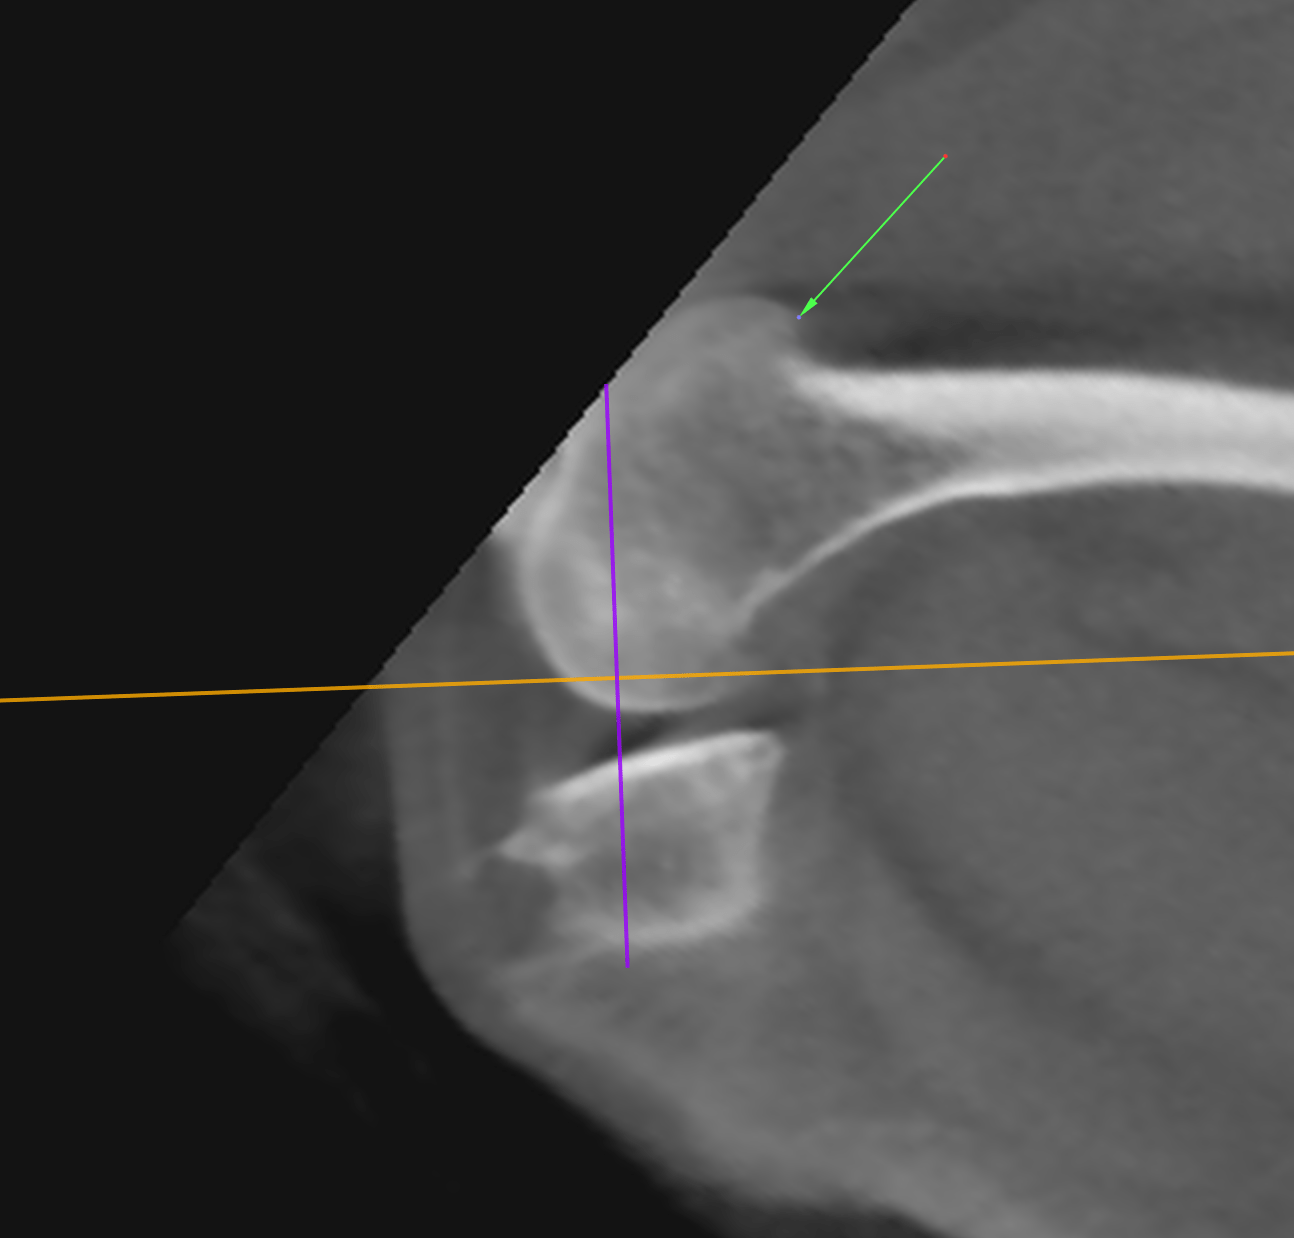

CT Degenerative Joint Disease of the Stifle and Vertebral Malformation

CT Degenerative Joint Disease of the Stifle and Vertebral Malformation Stifle In French See how “stifle” is translated from english to french with more examples in context Persévérer dans cette voie, c'est le meilleur moyen d'étouffer la. Stifle translated from english to french including synonyms, definitions, and related words. In this short article, we explain and provide some examples of the most common french verb tenses you'll come across. Forums pour discuter de. Stifle In French.

CT Degenerative Joint Disease of the Stifle and Vertebral Malformation Stifle In French Forums pour discuter de stifle, voir ses formes composées, des exemples et poser vos questions. Persévérer dans cette voie, c'est le meilleur moyen d'étouffer la. Stifle translated from english to french including synonyms, definitions, and related words. In this short article, we explain and provide some examples of the most common french verb tenses you'll come across. See how “stifle”. Stifle In French.

CT Degenerative Joint Disease of the Stifle and Vertebral Malformation Stifle In French Pursuing this path is the best way to stifle growth and to increase unemployment. Forums pour discuter de stifle, voir ses formes composées, des exemples et poser vos questions. In this short article, we explain and provide some examples of the most common french verb tenses you'll come across. See how “stifle” is translated from english to french with more. Stifle In French.